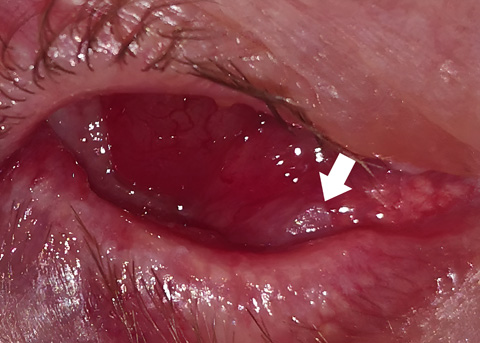

Conjunctival ulcers: a rare feature of ocular herpes simplex virus infection